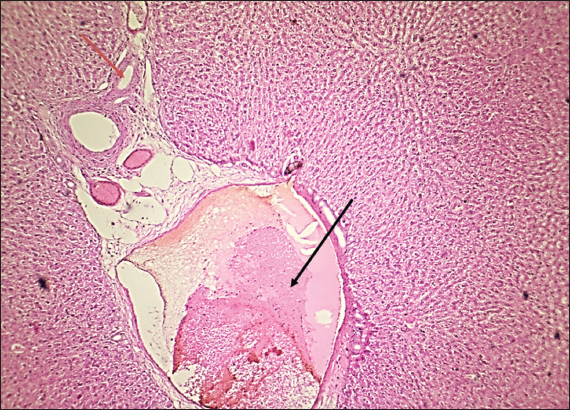

The results of this study revealed no significant differences in bilirubin levels in all treated animals (Table 1), whereas serum ALT and AST levels showed significant elevations in all treated animals either by citalopram alone (fourth group) or with J. regia pulp extract at doses of both 10 and 20 mg/kg (Tables 2 and 3). Sections of histopathological study appeared as mild degenerative lesions characterized by infiltration of fat droplets inside hepatic cells, which gave them a ring shape appearance due to pushing the nucleus at one side from the hepatic cells with fibrous networks formation in the tissue parenchyma, infiltration of structureless, homogenous, and pinkish material (Figs. 16). Clear hepatic vein congestion and narrowing in the hepatic artery and arteriole diameters revealed that citalopram caused liver dysfunction and injury (Figs. 79).

These results correspond with those of other studies, in which patients treated with antidepressants appeared to have moderately elevated levels of the aminotransferase. All antidepressants caused hepatotoxicity; citalopram is that have the least potential for hepatotoxicity, which is characterized by high alanine aminotransferase levels (Gartlehner et al., 2008; Voican et al., 2014; Ilgın et al., 2020). The results of this study revealed no significant differences in bilirubin levels in all treated animals as the level of p < 0.05, serum ALT and AST levels showed a significant elevation in all treated animals either by citalopram only (fourth group) or with J. regia pulp extract at doses of 10 and 20 mg/kg B.W. Sections of histopathological sections show mild degenerative lesions characterized by infiltration of fat droplets inside hepatic cells, which give them a ring shape appearance due to pushing the nucleus at one side from the hepatic cells with fibrous networks formation in the tissue parenchyma, infiltration of structureless, homogenous, and pinkish material (Figs. 4 and 6). Clear hepatic vein congestion and narrowing in the hepatic artery and arteriole diameters revealed that citalopram caused liver dysfunction and injury (Figs. 79).

Fig. 7. Histological section of the liver of rats drenched with 0.6 mg/kg citalopram. The section shows clear hepatic vein congestion (black arrows) narrowing of the hepatic artery and arteriole diameter (red arrows) (H and E stain 400X).

Fig. 9. Histological section of rat liver drenched with 20 mg/kg J. regia pulp extract. The section shows clear hepatic vein congestion (black arrow) narrowing of the hepatic artery and arteriole diameter (red arrow) (H and E stain 400X).